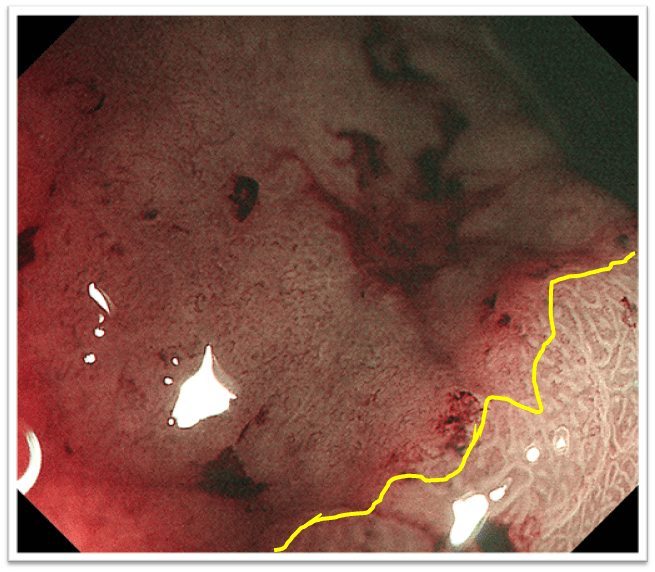

分流术后1月复查电子胃镜:门脉高压性胃病明显缓解何谓tips?